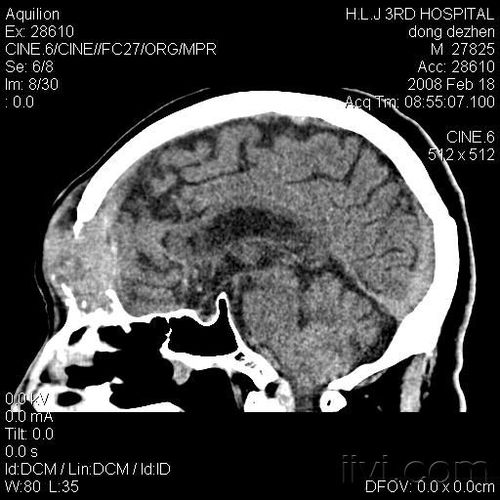

超急性期大面积脑梗死 ct 平扫表现

脑部CT图像

脑部ct图片

脑部ct

正常脑部ct图片